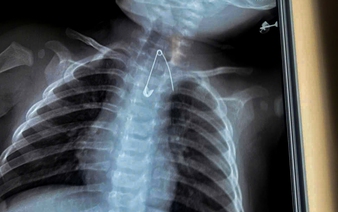

Tag: "lollipop stick"

Ca Mau Obstetrics and Pediatrics Hospital in southern Vietnam said on Thursday that its doctors had saved two young children who swallowed extremely dangerous foreign objects, including one case involving a perforated duodenum and another in which a sharp metal object became lodged dangerously close to the aorta.